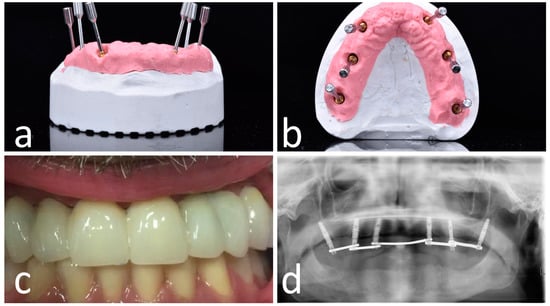

A CBCT (Scanora 3Dx) and an intraoral surface scan (IOS) were taken on each patient. An ideal virtual wax-up of teeth was completed by Lab Technician. Both DICOM files from CBCT and stereolithography (STL) files from the IOS were matched in Navident software and semi-automatically superimposed to residual teeth (or in toothless cases, using reference points in the wax-up) using the provided mesh-to-image registration tool. In addition, the STL files of the final teeth set-up were matched above previous IOS files of the baseline oral conditions and displayed in Navident software to perform prosthetically driven implant planning (Figure 1).

Figure 1.

Implant planning using stereolithography (STL) files as reference for a prosthetic driven implantation (a). Panoramic (b), axial (c), bucco-lingual (d), and parasagittal (e) view.